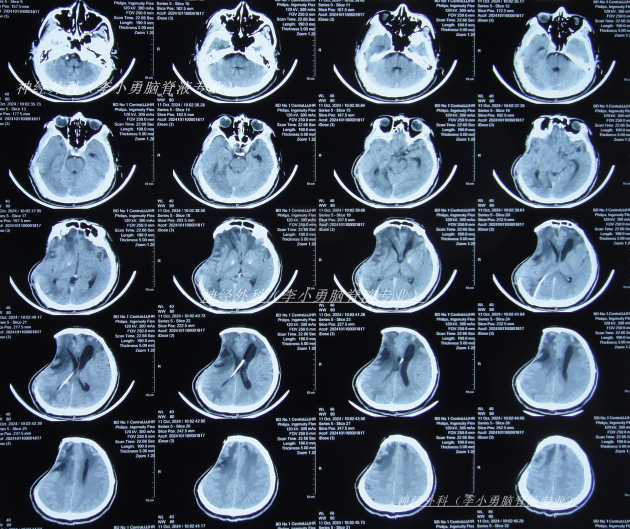

脑室腹腔分流术后13天即2024年10月2日,查头颅CT示去骨瓣术后,脑室分流术后状态,脑室仍有扩张(图-1);但意识有好转。

图-1:2024年10月2日头颅CT

脑室腹腔分流术后22天即2024年10月11日,查头颅CT示脑室缩小(图-2)。

图-2:2024年10月11日头颅CT